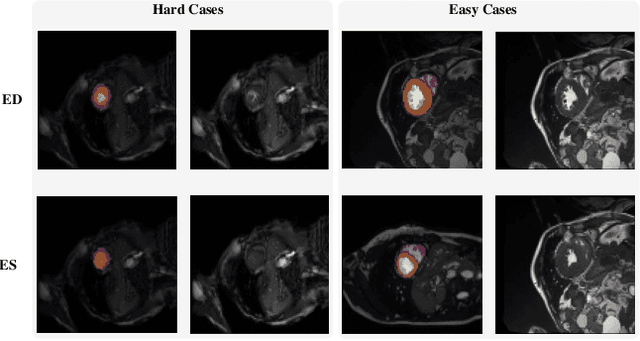

Abstract:Coronary artery disease (CAD) is the most common cause of death globally, and its diagnosis is usually based on manual myocardial segmentation of Magnetic Resonance Imaging (MRI) sequences. As the manual segmentation is tedious, time-consuming and with low applicability, automatic myocardial segmentation using machine learning techniques has been widely explored recently. However, almost all the existing methods treat the input MRI sequences independently, which fails to capture the temporal information between sequences, e.g., the shape and location information of the myocardium in sequences along time. In this paper, we propose a myocardial segmentation framework for sequence of cardiac MRI (CMR) scanning images of left ventricular cavity, right ventricular cavity, and myocardium. Specifically, we propose to combine conventional networks and recurrent networks to incorporate temporal information between sequences to ensure temporal consistent. We evaluated our framework on the Automated Cardiac Diagnosis Challenge (ACDC) dataset. Experiment results demonstrate that our framework can improve the segmentation accuracy by up to 2% in Dice coefficient.